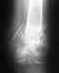

Неправильно срослась лодыжка

Более развернуто задайте вопрос. И приложите не многомегабайтный файл, а фото рентгенограмм (фас и профиль). Это 100-200 Кб, а не 18 Мб.